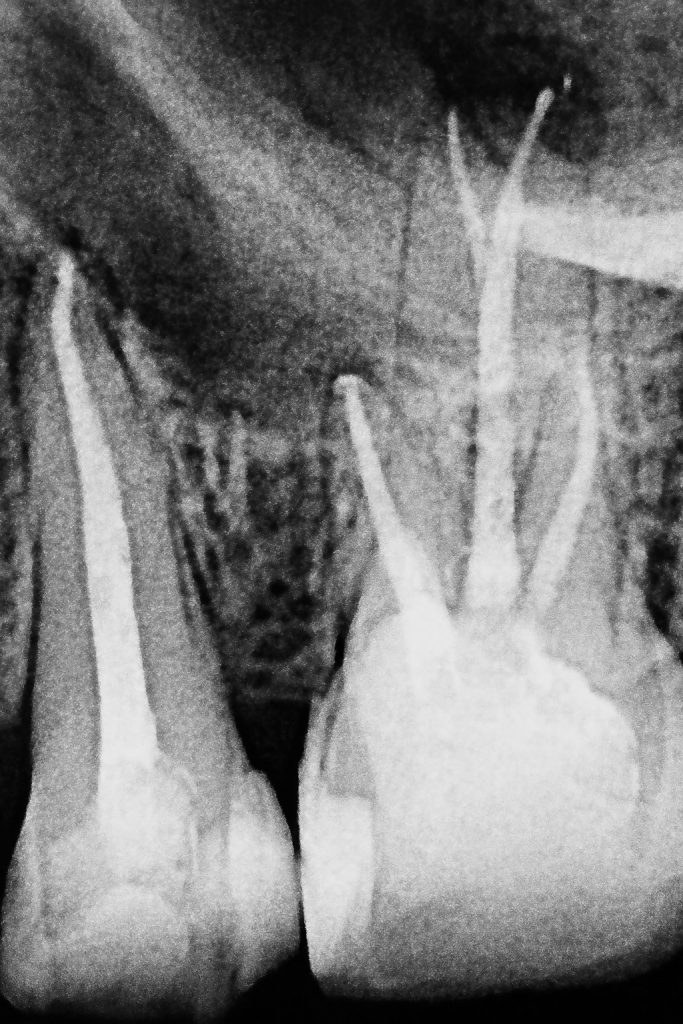

- Using pre-operative CBCT, the palatal root of the first molar was mapped for the suspected split.

- Under magnification, the canal division was identified and negotiated using C+ files and K-files #6–10 with EDTA gel.

- Working length was confirmed with an apex locator and radiographs.

- Rotary NiTi system was used for shaping; irrigants included 5.25 % NaOCl and 17 % EDTA, both sonically activated for effective disinfection. (Fig 3–4)